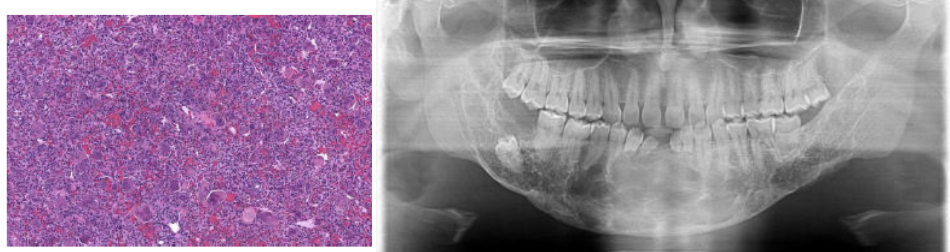

Identify the following:

A

Cementoblastoma

Give one diagnosis for this case:

Histology shows multinucleated giant cells

Answer: central giant cell granuloma